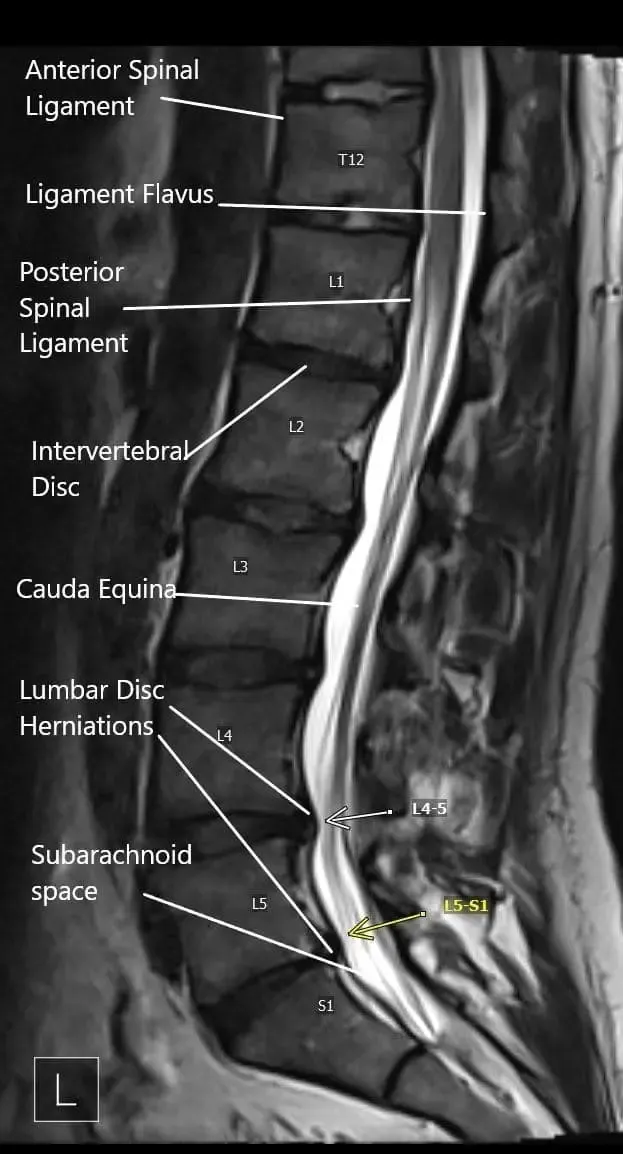

El nervio ciático está formado por raíces nerviosas de la parte inferior de la columna lumbar y sacra (L4-S3). Sale de la pelvis a través de la escotadura ciática mayor y desciende por la parte posterior del muslo, ramificándose en nervios más pequeños que controlan el movimiento y la sensibilidad de las piernas y los pies.

Cuando una hernia discal u otra alteración de la columna comprime una de estas raíces, la irritación resultante provoca los síntomas típicos de la ciática.

Sección axial de la resonancia magnética lumbosacra en el nivel L4-L5.

Corte sagital del lumbosacro en resonancia magnética.